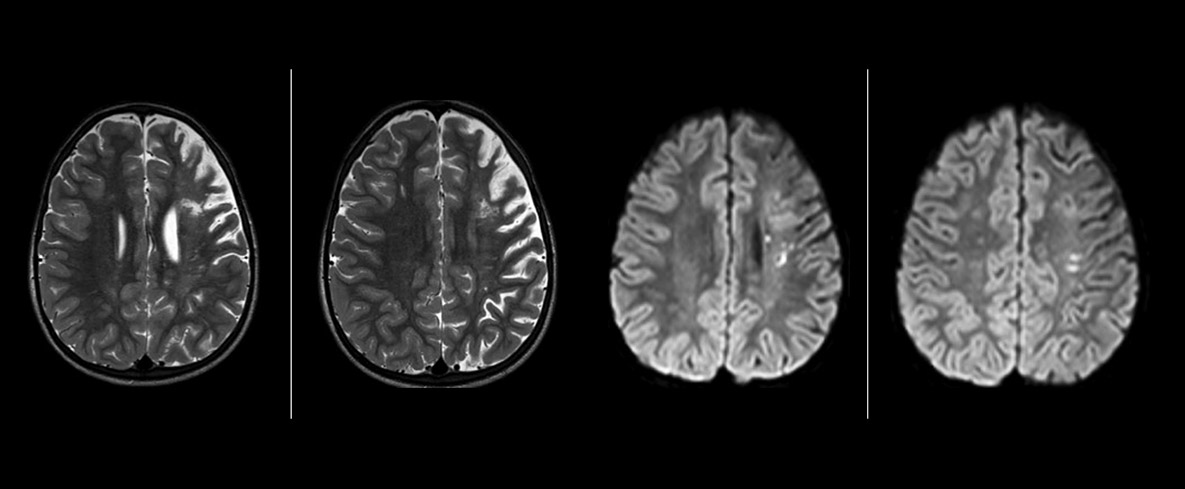

pCASL helps assess brain perfusion without contrast

Pseudo-continuous arterial spin labeling (pCASL) was developed for brain perfusion imaging without contrast agent. “This is very desirable in pediatric patients where the general trend is to limit the administration of contrast,” says Dr. Miller.

Dr. Miller uses pCASL for all patients who present with chronic and acute cerebrovascular abnormalities such as acute stroke, as well as patients who present with signs of acute inflammation in the brain, and occasionally in patients with tumors, to assess the perfusion status of their tumor.

“In combination with diffusion weighted imaging, it can help give a more extended assessment of the degree of perfusion abnormality in a patient who is suffering acute ischemia. We have a number of patients who have chronic arterial insufficiency due to prior arterial abnormalities or acquired arterial abnormalities such as sickle cell disease or neurofibromatosis. Sometimes the child’s first manifestation of disease progression is a reduction in brain perfusion before stroke symptoms manifest clinically or in diffusion weighted imaging. We use pCASL to help delineate the perfusion abnormality.”

“We built up confidence in pCASL by comparing it to contrast-based perfusion imaging. Once we had confidence that it was representing what the contrast perfusions were representing, we increased our diagnostic confidence by serial imaging in either the acute stage or the long term stages in a number of patients with arterial abnormalities.

To other new users I would recommend to also start to interpret the pCASL images in comparison with other standard imaging – T2 and FLAIR and DWI – until the user gains confidence in interpreting these images by themselves.”